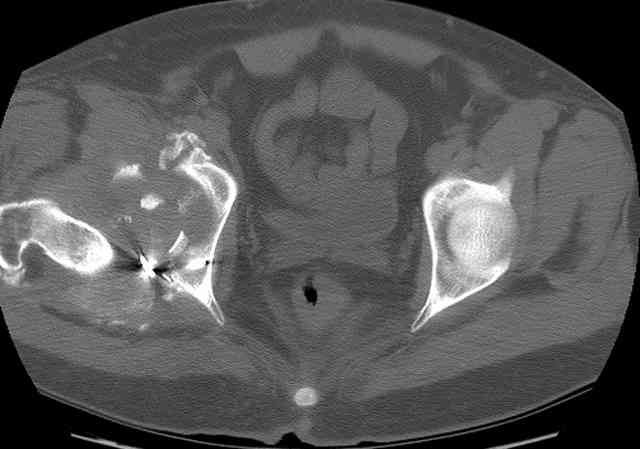

The 2nd example is of a motorcyclist with a transverse fracture-dislocation...he had a closed attempted reduction and placed in traction but the manipulative reduction was not concentric (not unusual for this injury pattern)...so the traction was adjusted to be just enough to disengage the head from the fracture (12#) until he could be cleared for surgery one day after injury...he was treated "urgently" then with a prone KL, clean the fracture, reduce and clamp it, screw it, support with a balanced plate, close, and enjoy...2-3hours, 400cc EBL, blah, blah, blah..